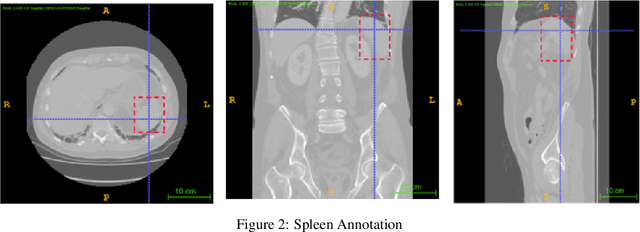

Abstract:Computer aided diagnostics often requires analysis of a region of interest (ROI) within a radiology scan, and the ROI may be an organ or a suborgan. Although deep learning algorithms have the ability to outperform other methods, they rely on the availability of a large amount of annotated data. Motivated by the need to address this limitation, an approach to localisation and detection of multiple organs based on supervised and semi-supervised learning is presented here. It draws upon previous work by the authors on localising the thoracic and lumbar spine region in CT images. The method generates six bounding boxes of organs of interest, which are then fused to a single bounding box. The results of experiments on localisation of the Spleen, Left and Right Kidneys in CT Images using supervised and semi supervised learning (SSL) demonstrate the ability to address data limitations with a much smaller data set and fewer annotations, compared to other state-of-the-art methods. The SSL performance was evaluated using three different mixes of labelled and unlabelled data (i.e.30:70,35:65,40:60) for each of lumbar spine, spleen left and right kidneys respectively. The results indicate that SSL provides a workable alternative especially in medical imaging where it is difficult to obtain annotated data.